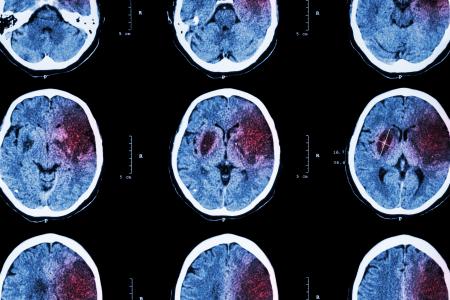

C’est un nouveau « coupable » immunitaire dans la maladie d'Alzheimer qui vient d’être découvert par cette équipe de neurologues de la Northwestern University : il s’agit des cellules immunitaires du cerveau et du liquide céphalo-rachidien qui deviennent dérégulées et se mettent « un peu en colère» -écrivent ces chercheurs, au fur et mesure que nous vieillissons. Ces travaux, publiés dans la revue Cell, suggèrent à nouveau que traiter ou bloquer l’inflammation du cerveau pourrait retarder considérablement la progression de la maladie.

Ce n’est pas la première étude à suggérer cette voie thérapeutique, mais c’est la première analyse approfondie du système immunitaire du cerveau. Au sein de ce système, les chercheurs rappellent le rôle du réservoir de liquide céphalo-rachidien (LCR), qui circule dans et autour du cerveau et de la moelle épinière. Cette barrière liquide entre le cerveau et le crâne joue un rôle de protection physique -contre les chocs-, mais exerce une autre fonction critique, moins connue : un rôle de protection immunitaire, qui reste mal compris.

L’étude décrypte ce rôle du LCR dans les troubles cognitifs, dont la maladie d'Alzheimer. Des travaux qui permettent de proposer un nouvel indice sur le processus de neurodégénérescence : l'équipe utilise le séquençage d'ARN unicellulaire pour modéliser 59 systèmes immunitaires associés aux LCR de 45 participants en bonne santé ; puis les chercheurs comparent ces résultats avec ceux du LCR de 14 adultes diagnostiqués avec troubles cognitifs. Cet examen révèle enfin :